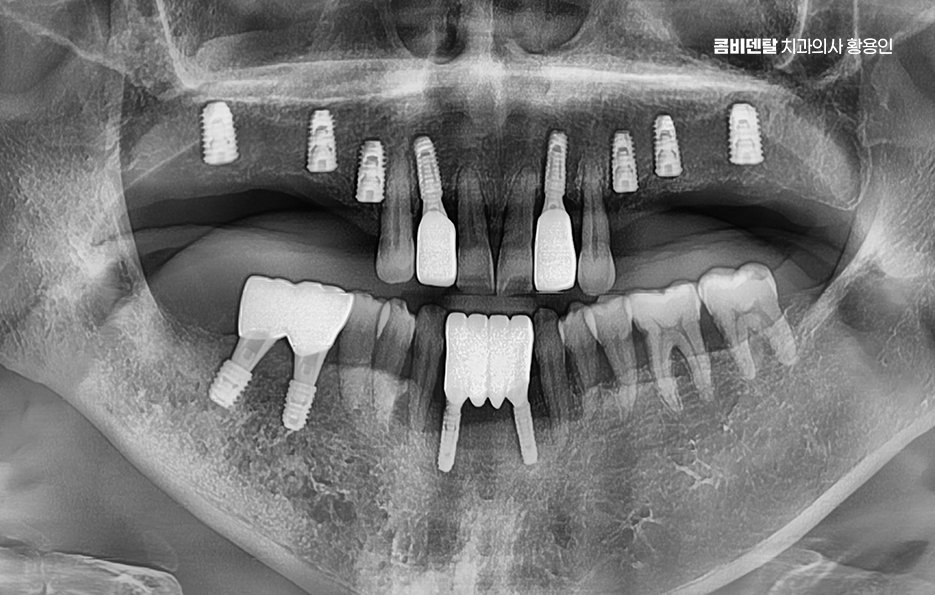

이런 상태를 “부분 무치악”이라고 부르는데 이러한 상태에서 50대임플란트 치료 계획을 세운다는 것은 전체 치열과 기능까지 다시 설계해야 하는 복잡한 치료가 될 수 있어서 50대에 여러 치아를 잃은 경우엔 임플란트 치료 계획이 단순한 ‘치아 대체’ 수준이 아니라, 전체적인 구강 재건이라는 개념으로 접근해야 할 수 있어요

50대임플란트 치료는 시작 전에 정밀한 진단이 선행되어야 하는데 단순히 빈자리만 보고 이 자리에 임플란트를 하나씩 심는 방식이 아니라 턱뼈 상태, 잇몸 높이, 씹는 힘의 분포, 전체 교합의 불균형까지 전부 고려해야 안정적이고 오래 가는 치료가 될 수 있어요

그래서 CT 촬영으로 턱뼈의 두께, 밀도, 신경 위치를 정밀하게 확인하고 각 임플란트의 위치와 각도를 계획해야 하며 50대는 전신 건강 상태도 함께 고려해야 하는데 당뇨, 고혈압, 골다공증 같은 만성 질환이 있는 경우에는 임플란트 치료 시 잇몸 치유 속도나 골융합 반응이 다를 수 있기 때문에, 반드시 의료진과의 충분한 상담이 필요하고 약물 복용 여부나 치유 능력 등을 고려해 치료 시기와 방식을 1:1 맞춤형으로 계획하실 필요가 있어요

군데군데 빠진 치아를 전부 임플란트로 하나씩 심을 수도 있지만, 꼭 그럴 필요는 없으며 예를 들어 어금니 3개가 빠졌다면 3개를 다 심지 않고, 2개만 심고 그 사이를 브릿지로 연결하는 방식도 가능한데 이러한 치료 계획은 단순히 효율성이나 경제적인 측면만 따지는 것이 아니라 각 개인의 잇몸 뼈 상태와 식립 위치, 각도 그리고 사후관리까지 종합적으로 판단해야 하기 때문에 경험 많은 치과의사와 함께 충분한 상의 후에 결정해야 하는 거예요